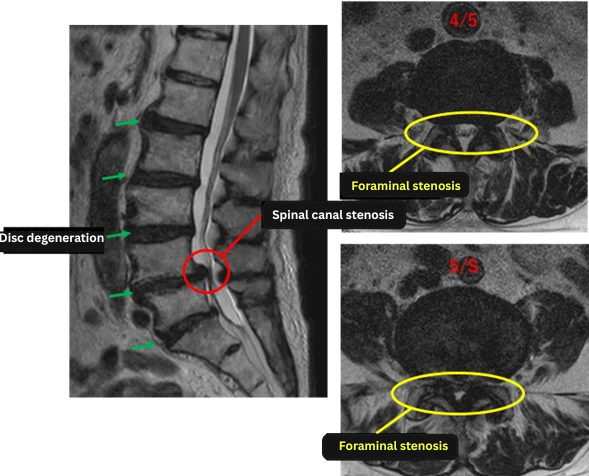

Imaging and findings

L1/2: Degeneration

L2/3: Degeneration, bulging

L3/4: Degeneration, bulging, left foraminal stenosis

L4/5: Degeneration, bulging, bilateral foraminal stenosis, lumbar spinal canal stenosis

L5/S: Degeneration, bulging

The above findings were also observed on the imaging.

Findings indicate spinal canal stenosis, disc degeneration, and foraminal stenosis at L2/3, L3/4, L4/5, and L5/S, which are likely the main causes of the patient’s symptoms.